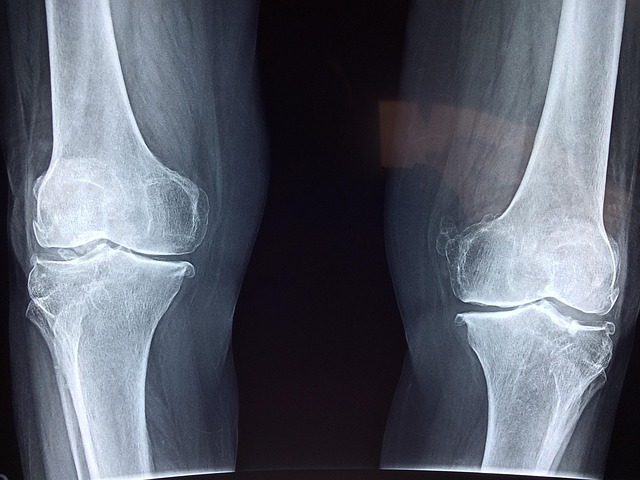

반응형40대가 넘으면 신체 곳곳에서 다양한 변화가 시작됩니다. 특히 폐경을 겪는 여성이라면 누구나 공감할 수 있는 변화 중 하나는 바로 ‘뼈의 약화’입니다. 겉으로는 아무 이상 없어 보이지만, 체내에서는 조용히 골밀도가 낮아지고 있다는 신호가 켜지고 있죠. 이러한 골다공증의 주요 방어막이 되어주는 것이 바로 칼슘과 비타민D입니다. 이 두 영양소는 서로 깊이 연결되어 있으며, 각자 중요한 역할과 복용 시 유의할 점이 존재합니다.

40대부터는 여성의 경우 폐경으로 인해 에스트로겐이 급감하면서 골밀도가 빠르게 줄어듭니다.

- 특히 폐경 후 3~5년 내에 뼈 손실이 가장 급격하게 일어나며,

- 남성도 테스토스테론의 감소로 인해 골감소증이 시작됩니다.

→ 특히 40대 여성의 경우, 골반뼈, 척추, 대퇴골 부위의 골절 위험이 커지며, 낙상 후 회복에 오랜 시간이 걸릴 수 있어요.

→ 폐경 이후에는 골밀도 손실이 급속도로 진행되기 때문에, 칼슘은 선택이 아닌 필수입니다.

골다공증은 어느 날 갑자기 나타나는 것이 아니라, 오랜 시간 소리 없이 진행되는 질환입니다.